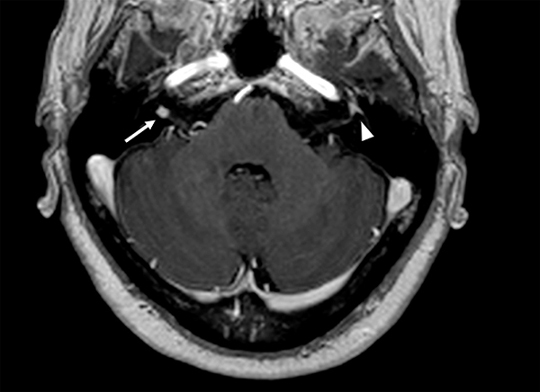

Preparado anatómico. Cortes sagital y coronal mostrando las estructuras del anillo de Waldeyer. Se demarcan las principales estructuras que conforman el anillo de Waldeyer: amígdalas palatinas (flechas largas), amígdalas faríngeas o adenoides (flecha corta) y amígdalas linguales (cabeza de flecha).

Cortes sagital y coronal de TC de la faringe. Paciente de 16 años asintomática. Se demarca la hipertrofia fisiológica de las principales estructuras que conforman el anillo de Waldeyer: amígdalas palatinas (flechas largas), amígdalas faríngeas o adenoides (flecha corta) y amígdalas linguales (cabeza de flecha).